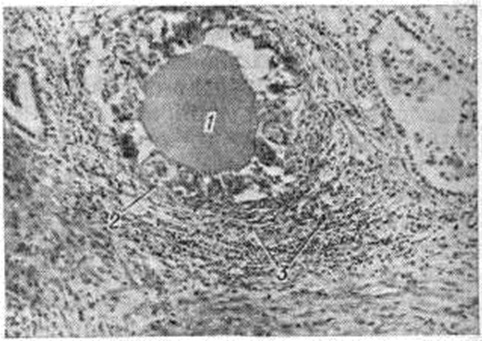

Болеют чаще женщины в возрасте 20—50 лет, редко дети. Подострый Тиреоидит развивается, как правило, в нормальной щитовидной железе и почти никогда — в в зобно-измененной. Этиология подострого Тиреоидит окончательно не выяснена, однако предполагают, что заболевание имеет вирусную природу, так как обычно оно развивается вскоре после вирусных инфекций — гриппа (смотри полный свод знаний), кори (смотри полный свод знаний), эпидемического паротита (смотри полный свод знаний: Паротит эпидемический) и другие, а в крови больных в разгаре болезни могут определяться антитела к соответствующим вирусам. В течении подострого Тиреоидит в зависимости от содержания в крови тиреоидных гормонов выделяют несколько стадий. В I стадии подострого Тиреоидит в результате нарушения целостности мембран тиреоцитов и фолликулов щитовидной железы и выхода их содержимого в строму железы в крови повышается концентрация тироксина (смотри полный свод знаний) — Т4 и трийодтиронина (смотри полный свод знаний) — Т3, а также негормональных соединений йода, что увеличивает разницу между количеством белково-связанного йода (смотри полный свод знаний) и бутанолэкстрагируемого йода (смотри полный свод знаний) и блокирует захват йода щитовидной железой. Строма щитовидной железы инфильтрирована сегментоядерными лейкоцитами, лимфоцитами и тканевыми макрофагами. У некоторых больных в крови появляются антитиреоидные антитела. Во II стадии происходит снижение интенсивности деструктивных процессов в щитовидной железе, что ведёт к уменьшению концентрации негормональных соединений йода в крови и восстановлению механизма захвата йода железой. В строме железы отмечается скудная инфильтрация макрофагами и лимфоцитами с примесью плазматических клеток и исчезновение нейтрофилов. Массы излившегося в строму из разрушенных фолликулов коллоида окружены гистиоцитами и гигантскими клетками (смотри полный свод знаний), сходными с так называемый клетками инородных тел (рисунок 1). Для III стадии в связи с уменьшением объёма функционирующей железистой ткани характерны понижение содержания в крови тиреоидных гормонов и иногда транзиторный гипотиреоз. В этой стадии воспалительный процесс стихает, выявляются очаги регенерации фолликулов. В IV стадии — стадии выздоровления — нередко отмечается повышенный захват йода железой, которая прежде была обеднена им, поэтому данное явление носит компенсаторный характер. В то же время содержание Т3 и Т4 в крови снижено или находится в норме. При электронно-микроскопическом исследовании щитовидной железы у больных подострым тиреоидитом III —IV стадии отмечают признаки повышения функциональной активности тиреоцитов, но апикальных псевдоподий, содержащих капли коллоида, нет, а гигантские клетки мезенхимного происхождения представляют собой группы гистиоцитов без признаков фагоцитоза частиц коллоида. В конце стадии выздоровления все показатели нормализуются. Клинические, картина подострого Тиреоидит характеризуется острым началом, появлением болей, часто интенсивных, в области щитовидной железы, иррадиирующих в уши, нижнюю челюсть, затылок и шею. Иногда отмечают боль при глотании и повороте головы. Общее самочувствие ухудшается, температура тела повышена (иногда значительно). Щитовидная железа увеличена диффузно или очагово (чаще увеличивается одна её доля), плотна на ощупь, резко болезненна при пальпации. Иногда в начале поражается одна доля (чаще правая) с последующим вовлечением в процесс другой доли железы. Кожа над щитовидной железой горячая на ощупь. Регионарные лимфатических, узлы не увеличены. РОЭ обычно ускорена, иногда до 60— 90 миллиметров/час, может наблюдаться лимфоцитоз, лейкоцитарная формула обычно не изменена, количество лейкоцитов в норме, в сыворотке крови повышено относительное содержание γ-глобулинов и фибриногена. Характерным признаком подострого Тиреоидит является снижение захвата железой 131I. На последующих стадиях функциональные способности и состояние щитовидной железы постепенно нормализуются. Общее самочувствие также возвращается к норме. Продолжительность подострого Тиреоидит от 1 месяцев до 1½—2 лет. Диагноз устанавливают на основании характерной клинические, картины (плотная, болезненная щитовидная железа, не спаянная с окружающими тканями при интактных регионарных лимфатических, узлах), результатов лабораторный исследований, а также анамнестических данных (перенесенное 6—8 недель назад вирусное заболевание и другие). Подтверждает диагноз блокада захвата щитовидной железой 131I. Дифференциальный диагноз проводят с острым гнойным Тиреоидит в основном по характеру гемограммы (отсутствие лейкоцитоза), с ангиной (смотри полный свод знаний), при которой отсутствуют характерные изменения щитовидной железы, с диффузным токсическим зобом (смотри полный свод знаний: Зоб диффузный токсический) и токсической аденомой щитовидной железы. С опухолями щитовидной железы, которые также могут сопровождаться выраженным болевым синдромом, подострый Тиреоидит дифференцируют по показателям функциональной активности железы, в том числе по захвату ею 131I, а также по отсутствию спаяния с соседними тканями шеи и местного лимфаденита (см..). Диагностически важным тестом служит реакция на лечение глюкокортикоидами, высокие дозы которых (до 60 миллиграмм преднизолона в сутки) в течение 14— 18 дней приводят к улучшению состояния больного подострым тиреоидитом. В дифференциальной диагностике со специфическим Тиреоидит при туберкулёзе (смотри полный свод знаний) и сифилисе (смотри полный свод знаний) важную роль играют реакции Манту (смотри полный свод знаний: Туберкулинодиагностика) и Вассермана (смотри полный свод знаний: Вассермана реакция), а также данные биопсии (смотри полный свод знаний). Лечение подострого Тиреоидит обычно консервативное, назначают в основном преднизолон (начальная доза 20—30 миллиграмм в сутки). Уменьшение дозы преднизолона часто вызывает рецидив заболевания, поэтому постепенное снижение дозы следует проводить под постоянным контролем РОЭ и наличия болевого синдрома. Уменьшать дозу преднизолона при отсутствии болезненности в щитовидной железе надо приблизительно на 5 миллиграмм каждые 7—10 дней, однако все-таки основным показателем служит снижение РОЭ. В лёгких случаях можно ограничиться назначением салицилатов (ацетилсалициловой кислоты 2—4 грамм и более в сутки) или индометацина, бруфена, бутадиона, амидопирина. Назначение антибиотиков и антитиреоидных средств неэффективно. Прогноз благоприятный; как правило, наступает выздоровление. Рецидивы и упорное течение заболевания могут привести к склерозу щитовидной железы и, как следствие, к гипотиреозу. Хронический тиреоидит. К хронический Тиреоидит относят лимфоцитарный (аутоиммунный) Тиреоидит, или болезнь Хасимото (смотри полный свод знаний: Хасимото болезнь), фиброзно-инвазивный Тиреоидит и специфические Тиреоидит Фиброзно-инвазивный тиреоидит [синонимы: тиреоидит Риделя (наиболее употребимый синоним), зоб Риделя, деревянистый тиреоидит, хронический инвазивный тиреоидит, хронический фиброзный тиреоидит] — заболевание неясной этиологии, при котором паренхиму щитовидной железы замещает фиброзная ткань. Впервые описан в 1896 год Б. Риделем. Фиброзно-инвазивный Тиреоидит чаще встречается у лиц старше 50 лет, преимущественно у женщин. По данным, приведенным в 1957 год Вулнером (L. В. Woolner) и другие, он выявлен у 0,05% больных, оперированных по поводу заболеваний щитовидной железы. Щитовидная железа увеличена, плотная и при выраженном процессе кольцом охватывает трахею. Паренхиматозные элементы имеют вид отдельных островков в фиброзной, иногда гиалинизированной соединительной ткани (рисунок 2). Отмечают полное исчезновение дольчатости. Тиреоциты сохранившихся фолликулов уплощены. Коллоида в просвете фолликулов нет или его очень мало. Выявляются очаговые лимфоидные скопления, иногда с примесью многоядерных гигантских клеток. Фиброз при фиброзно-инвазивном Тиреоидит носит агрессивный характер и характеризуется обширными разрастаниями фиброзной ткани. Последняя распространяется за пределы капсулы щитовидной железы и поражает соседние мышцы, нервы, сосуды, нередко сочетается с идиопатическим фиброзом других областей (ретроперитонеальным, медиастинальным и другие). При фиброзно-инвазивном Тиреоидит происходит смещение и сдавление трахеи, в результате которого развивается выраженное изменение голоса. При вовлечении в процесс обоих возвратных гортанных нервов может развиться паралич гортани. Иногда фиброз распространяется на средостение. Больные жалуются на сдавление в области шеи, затруднение дыхания и глотания. Кожа над щитовидной железой не изменена и легко собирается в складки. Осложнением фиброзно-инвазивного Тиреоидит может быть гипотиреоз, хотя неповрежденные участки паренхимы щитовидный железы обычно обеспечивают эутиреоидное состояние. Фиброзно-инвазивный Тиреоидит может сочетаться с фиброзом околоушных желёз, языка, ретробульбарным и ретроперитонеальным фиброзом (синдромом Ормонда). Диагноз ставят на основании специфической клинические, картины, наличия плотного зоба (смотри полный свод знаний), спаянного с окружающими тканями и медленно увеличивающегося в размерах. При сканировании железы обнаруживают так называемый холодные очаги. Тиреоидные аутоантитела определяют редко и в низких титрах. Диагностически особенно информативна биопсия щитовидной железы. Дифференциальный диагноз с амилоидозом и раком щитовидной железы основывается главным образом на результатах гистологический исследования. От узлового нетоксического зоба фиброзно-инвазивный Тиреоидит отличает чрезвычайная плотность щитовидной железы и её спаяние с соседними тканями; от болезни Хасимото — спаяние зоба с соседними тканями, отсутствие в организме выраженных иммуно л. сдвигов, редкое и позднее развитие гипотиреоза; от подострого Тиреоидит— течение заболевания. отсутствие специфических изменений картины крови, характерных для подострого Тиреоидит, отсутствие болевого синдрома и спаяние зоба с соседними тканями. Лечение оперативное. Показаниями к операции являются большие размеры зоба, смещение и сдавление соседних органов. При диффузном поражении рекомендуется удаление части обеих долей и экстирпация перешейка железы, при одностороннем процессе — резекция соответствующей доли. Оперативное удаление частей щитовидной железы, кроме того, задерживает фиброз. Описаны случаи спонтанного прекращения такого процесса, а также обратного его развития после биопсии железы. При развившемся гипотиреозе необходима заместительная терапия тиреоидными гормонами. Прогноз при наличии симптомов сдавления зависит от своевременности операции, так как при значительном прорастании фиброзной ткани в соседние органы послеоперационный период может протекать особенно тяжело. Специфические тиреоидиты (туберкулезный, сифилитический, актиномикозный и другие) встречаются крайне редко и обычно являются локальными проявлениями системных заболеваний. Туберкулёзный Тиреоидит развивается в результате гематогенной диссеминации. Щитовидная железа имеет плотную консистенцию, иногда с бугристой поверхностью. В ней обнаруживаются туберкулёзные гранулемы или более крупные казеозные очаги, окруженные специфической грануляционной тканью. Характерно увеличение регионарных лимфатических, узлов. Обнаружение первичного очага и положительные реакции на туберкулин позволяют поставить правильный диагноз. При сифилитическом Тиреоидит щитовидная железа плотна и малоподвижна в связи с её сращением с окружающими тканями. Диагноз подтверждается положительными серологический пробами. При актиномикозе (смотри полный свод знаний) щитовидная железа вначале уплотняется, затем появляются характерные свищи и гной. Обнаружение в гное друз актиномицетов позволяет подтвердить диагноз. Лечение специфических Тиреоидит направлено на основное заболевание. Прогноз зависит от своевременной диагностики и рационального лечения. Смотри полный свод знаний: Щитовидная железа.